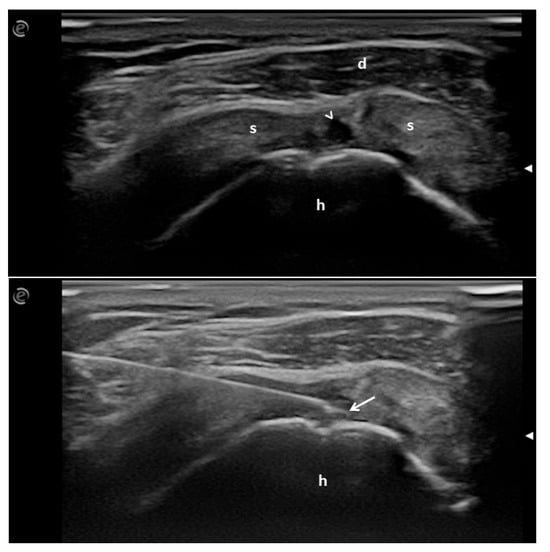

Figure A1. Longitudinal view of the supraspinatus tendon. a. Partial tendon tear (arrowhead). b. The arrow points to the tip of the needle placed within the tendon lesion. h = humeral head; s = supraspinatus tendon; d = deltoid muscle.

A rheumatologist used a free-hand and direct US-guided anterolateral in-plane approach to visualize the correct needle tip placement and the LWP injection within the tendon tear. A specific medical device was used (pre-prepared sterile disposable syringe with 5 mg/mL 1 mL of hydrolyzed bovine LWP solution, Tiss’You Srl RSM) to inject the LWPs into the intratendinous lesion. A 22-gauge needle was used. The correctness of the procedure and the spreading of the LWP solution was verified by real-time US assessment (Figure A1).